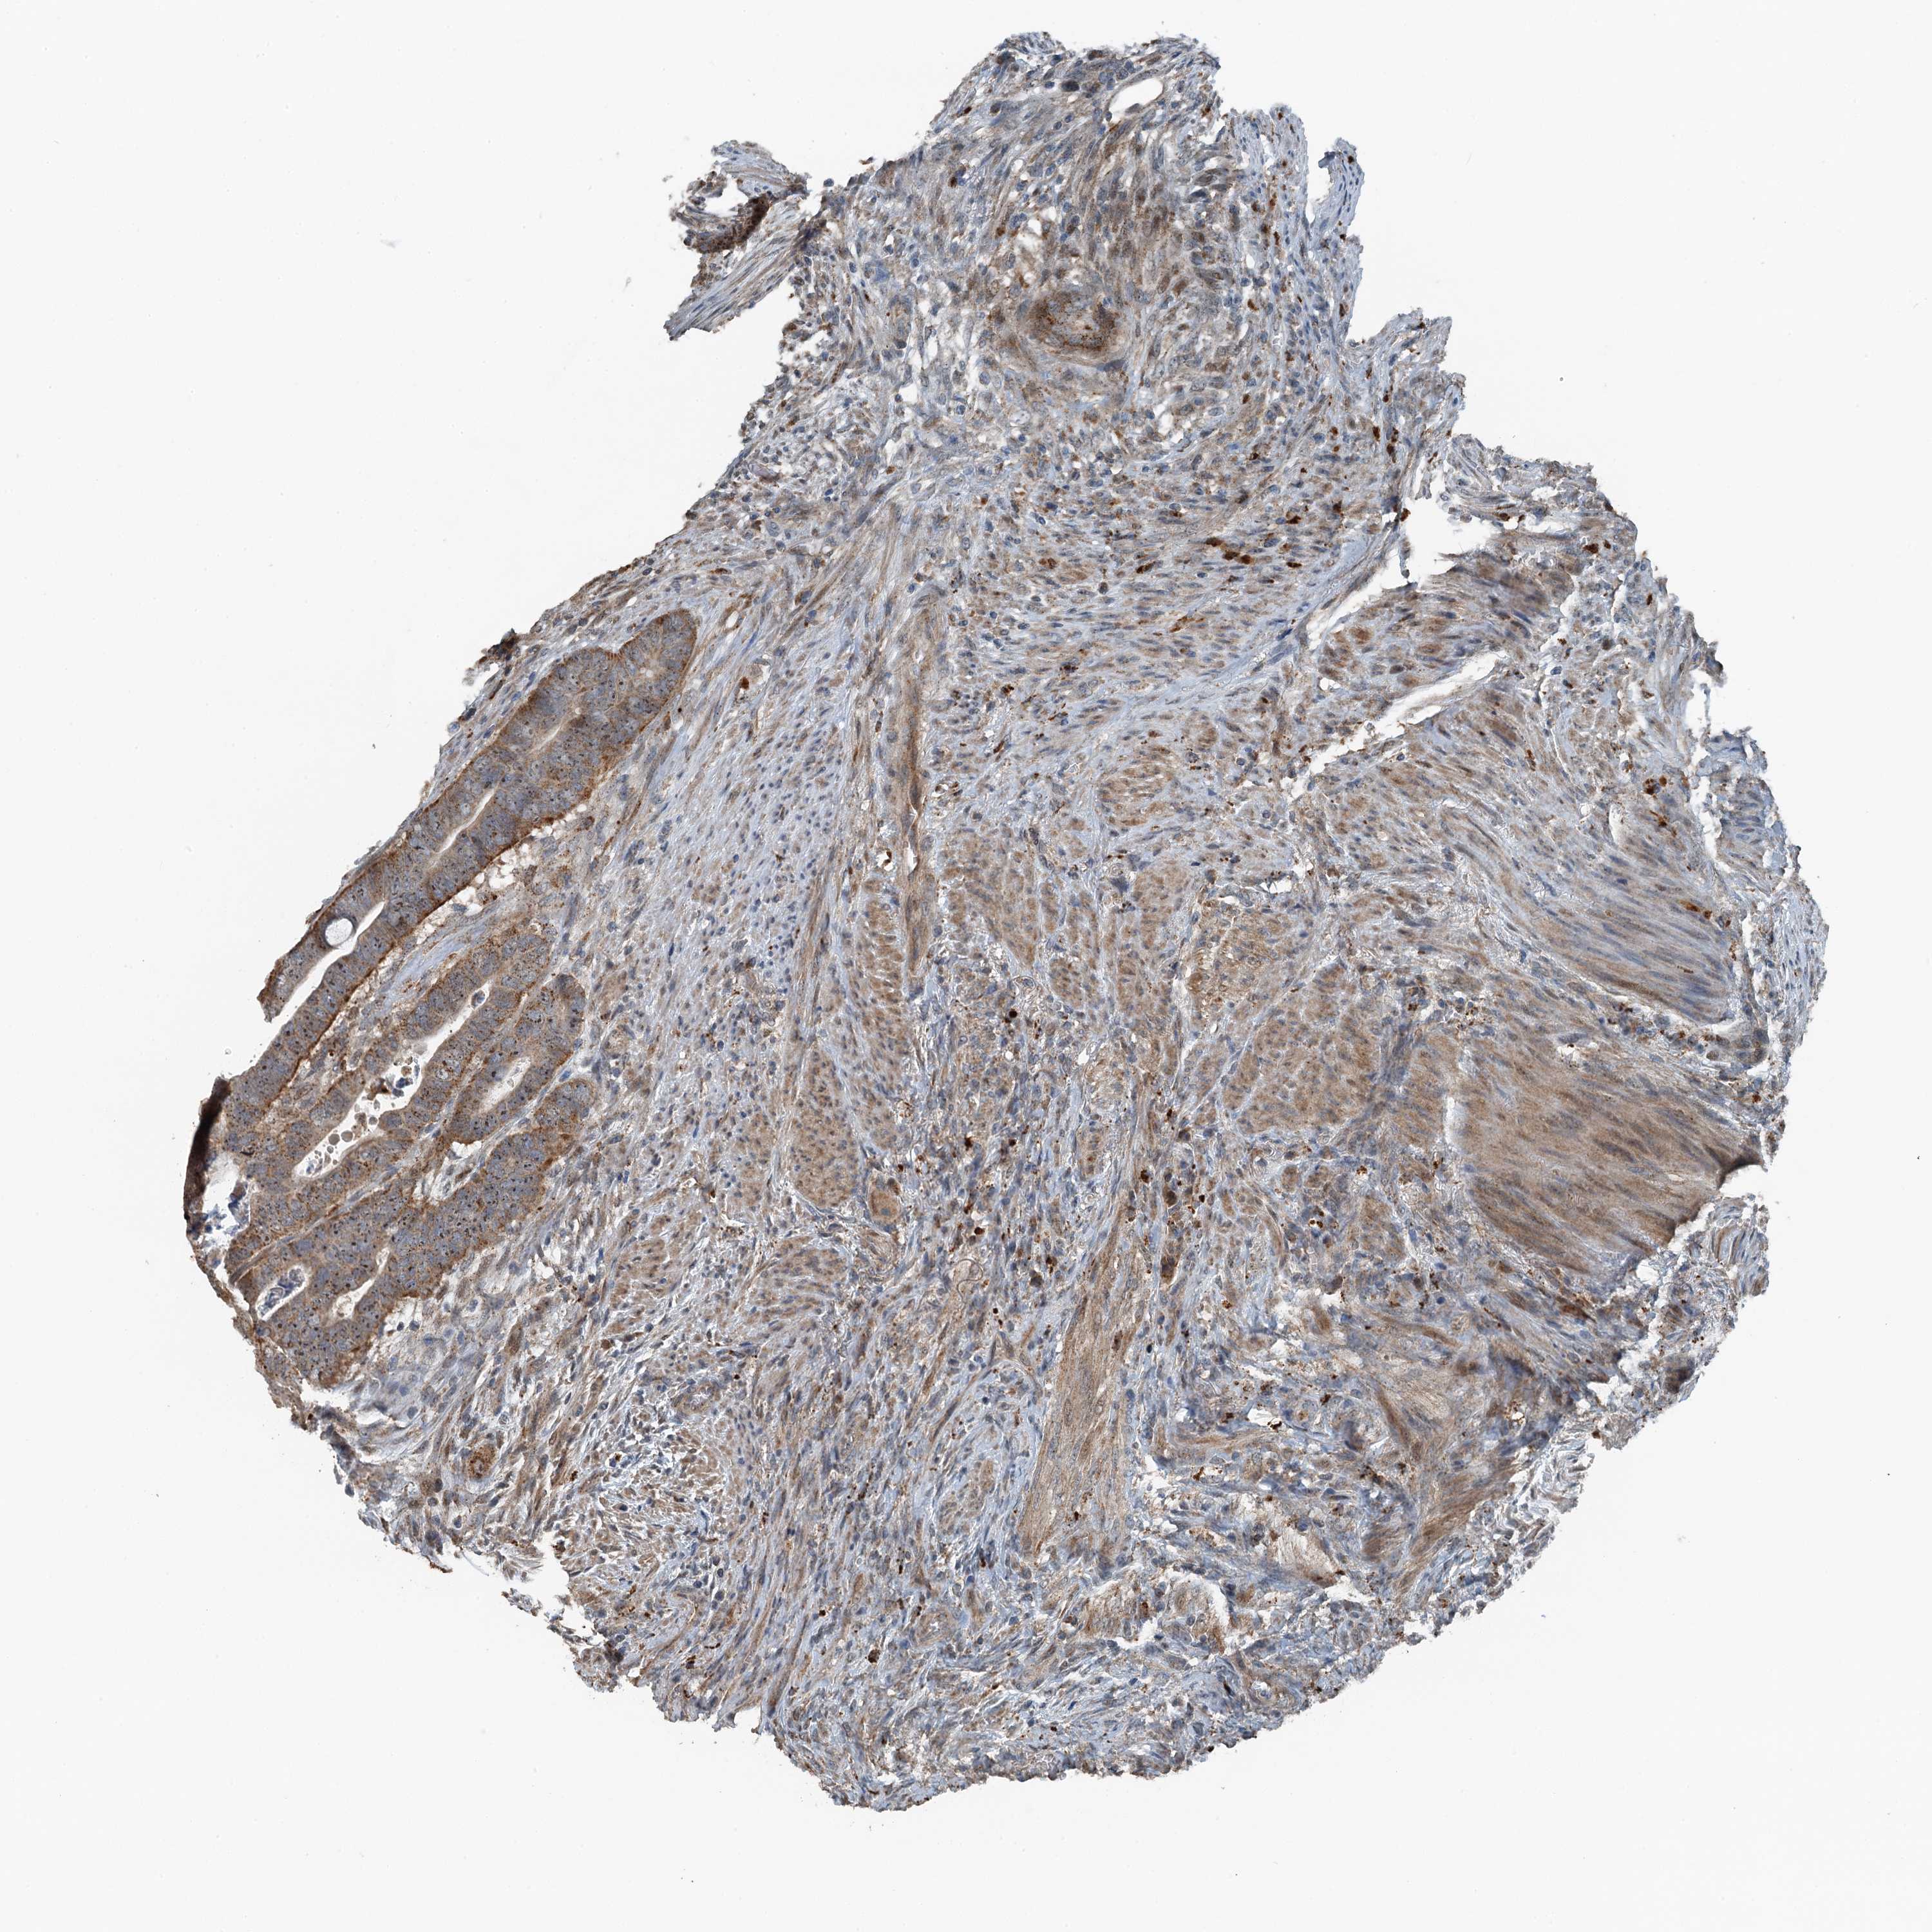

CANCER COLORECTAL CANCER Show tissue menu

Colorectal cancer

Human cancer

Colon adenocarcinoma